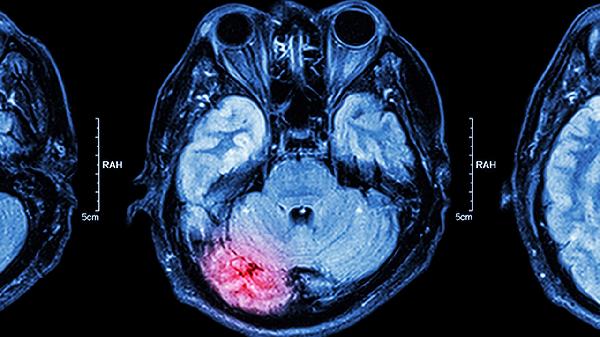

預防腦供血不足可通過控制血壓、合理飲食、適度運動、戒煙限酒、定期體檢等方式實現。腦供血不足可能與動脈硬化、高血壓、頸椎病等因素有關,通常表現為頭暈、頭痛、視物模糊等癥狀。

預防腦供血不足需建立健康生活方式,保持規(guī)律作息和樂觀心態(tài)。冬季注意頭部保暖,避免寒冷刺激誘發(fā)血管痙攣。出現持續(xù)頭暈、肢體麻木等癥狀時應盡早就醫(yī),完善經顱多普勒或頭顱MRI檢查。糖尿病患者需嚴格控糖,高血脂患者堅持服用降脂藥物,多學科協(xié)作管理可有效維護腦部供血。